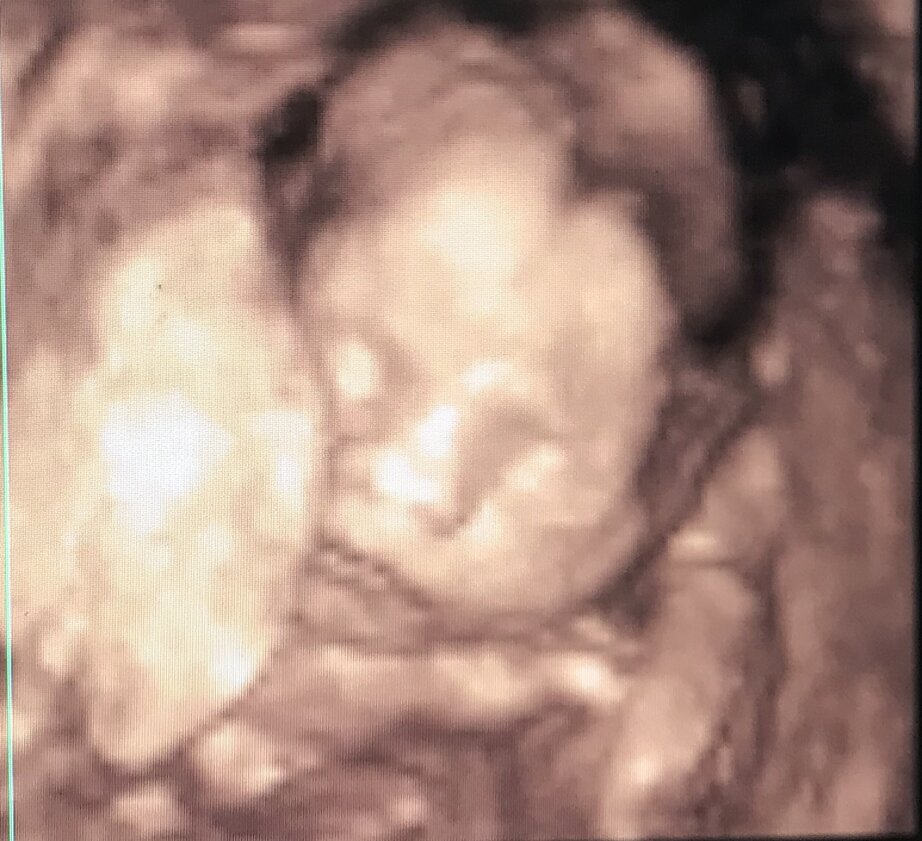

ECOGRAFIA 3D 4D